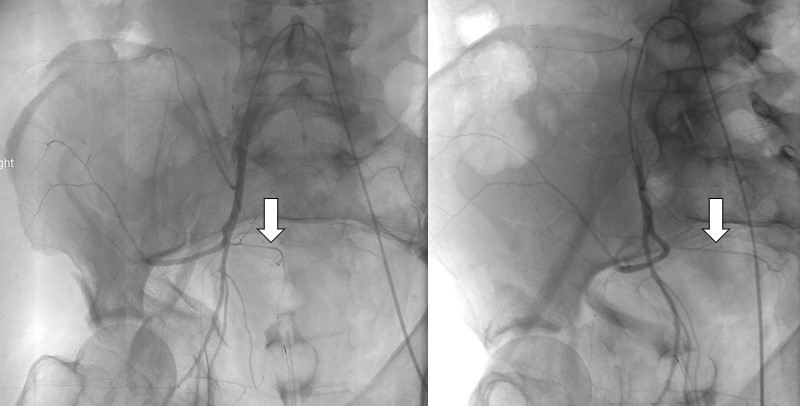

IVC stenosis and stent placement

the presence of venous collaterals indicates hemodynamically significant stenosis